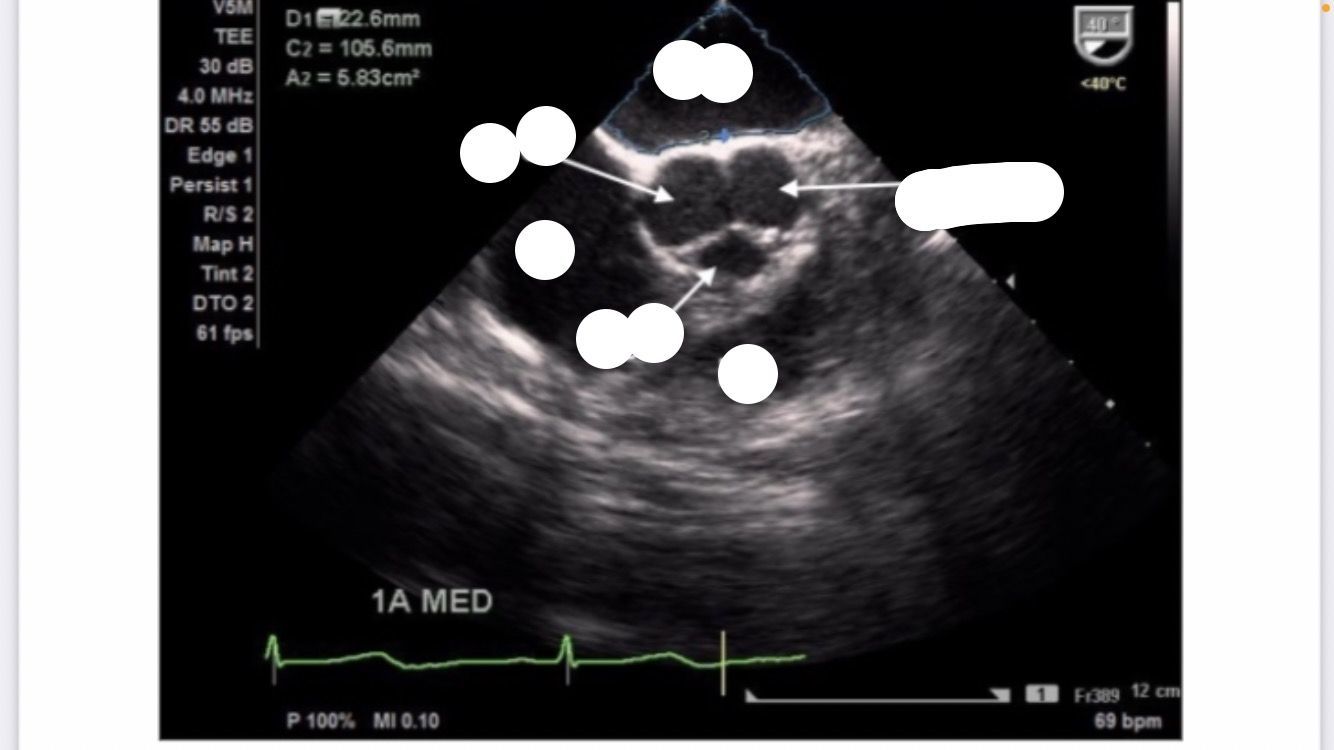

Mid-esophageal AV SAX

midesophageal aortic valve short axis

aortic stenosis

AV doesnt move between systole and diastole